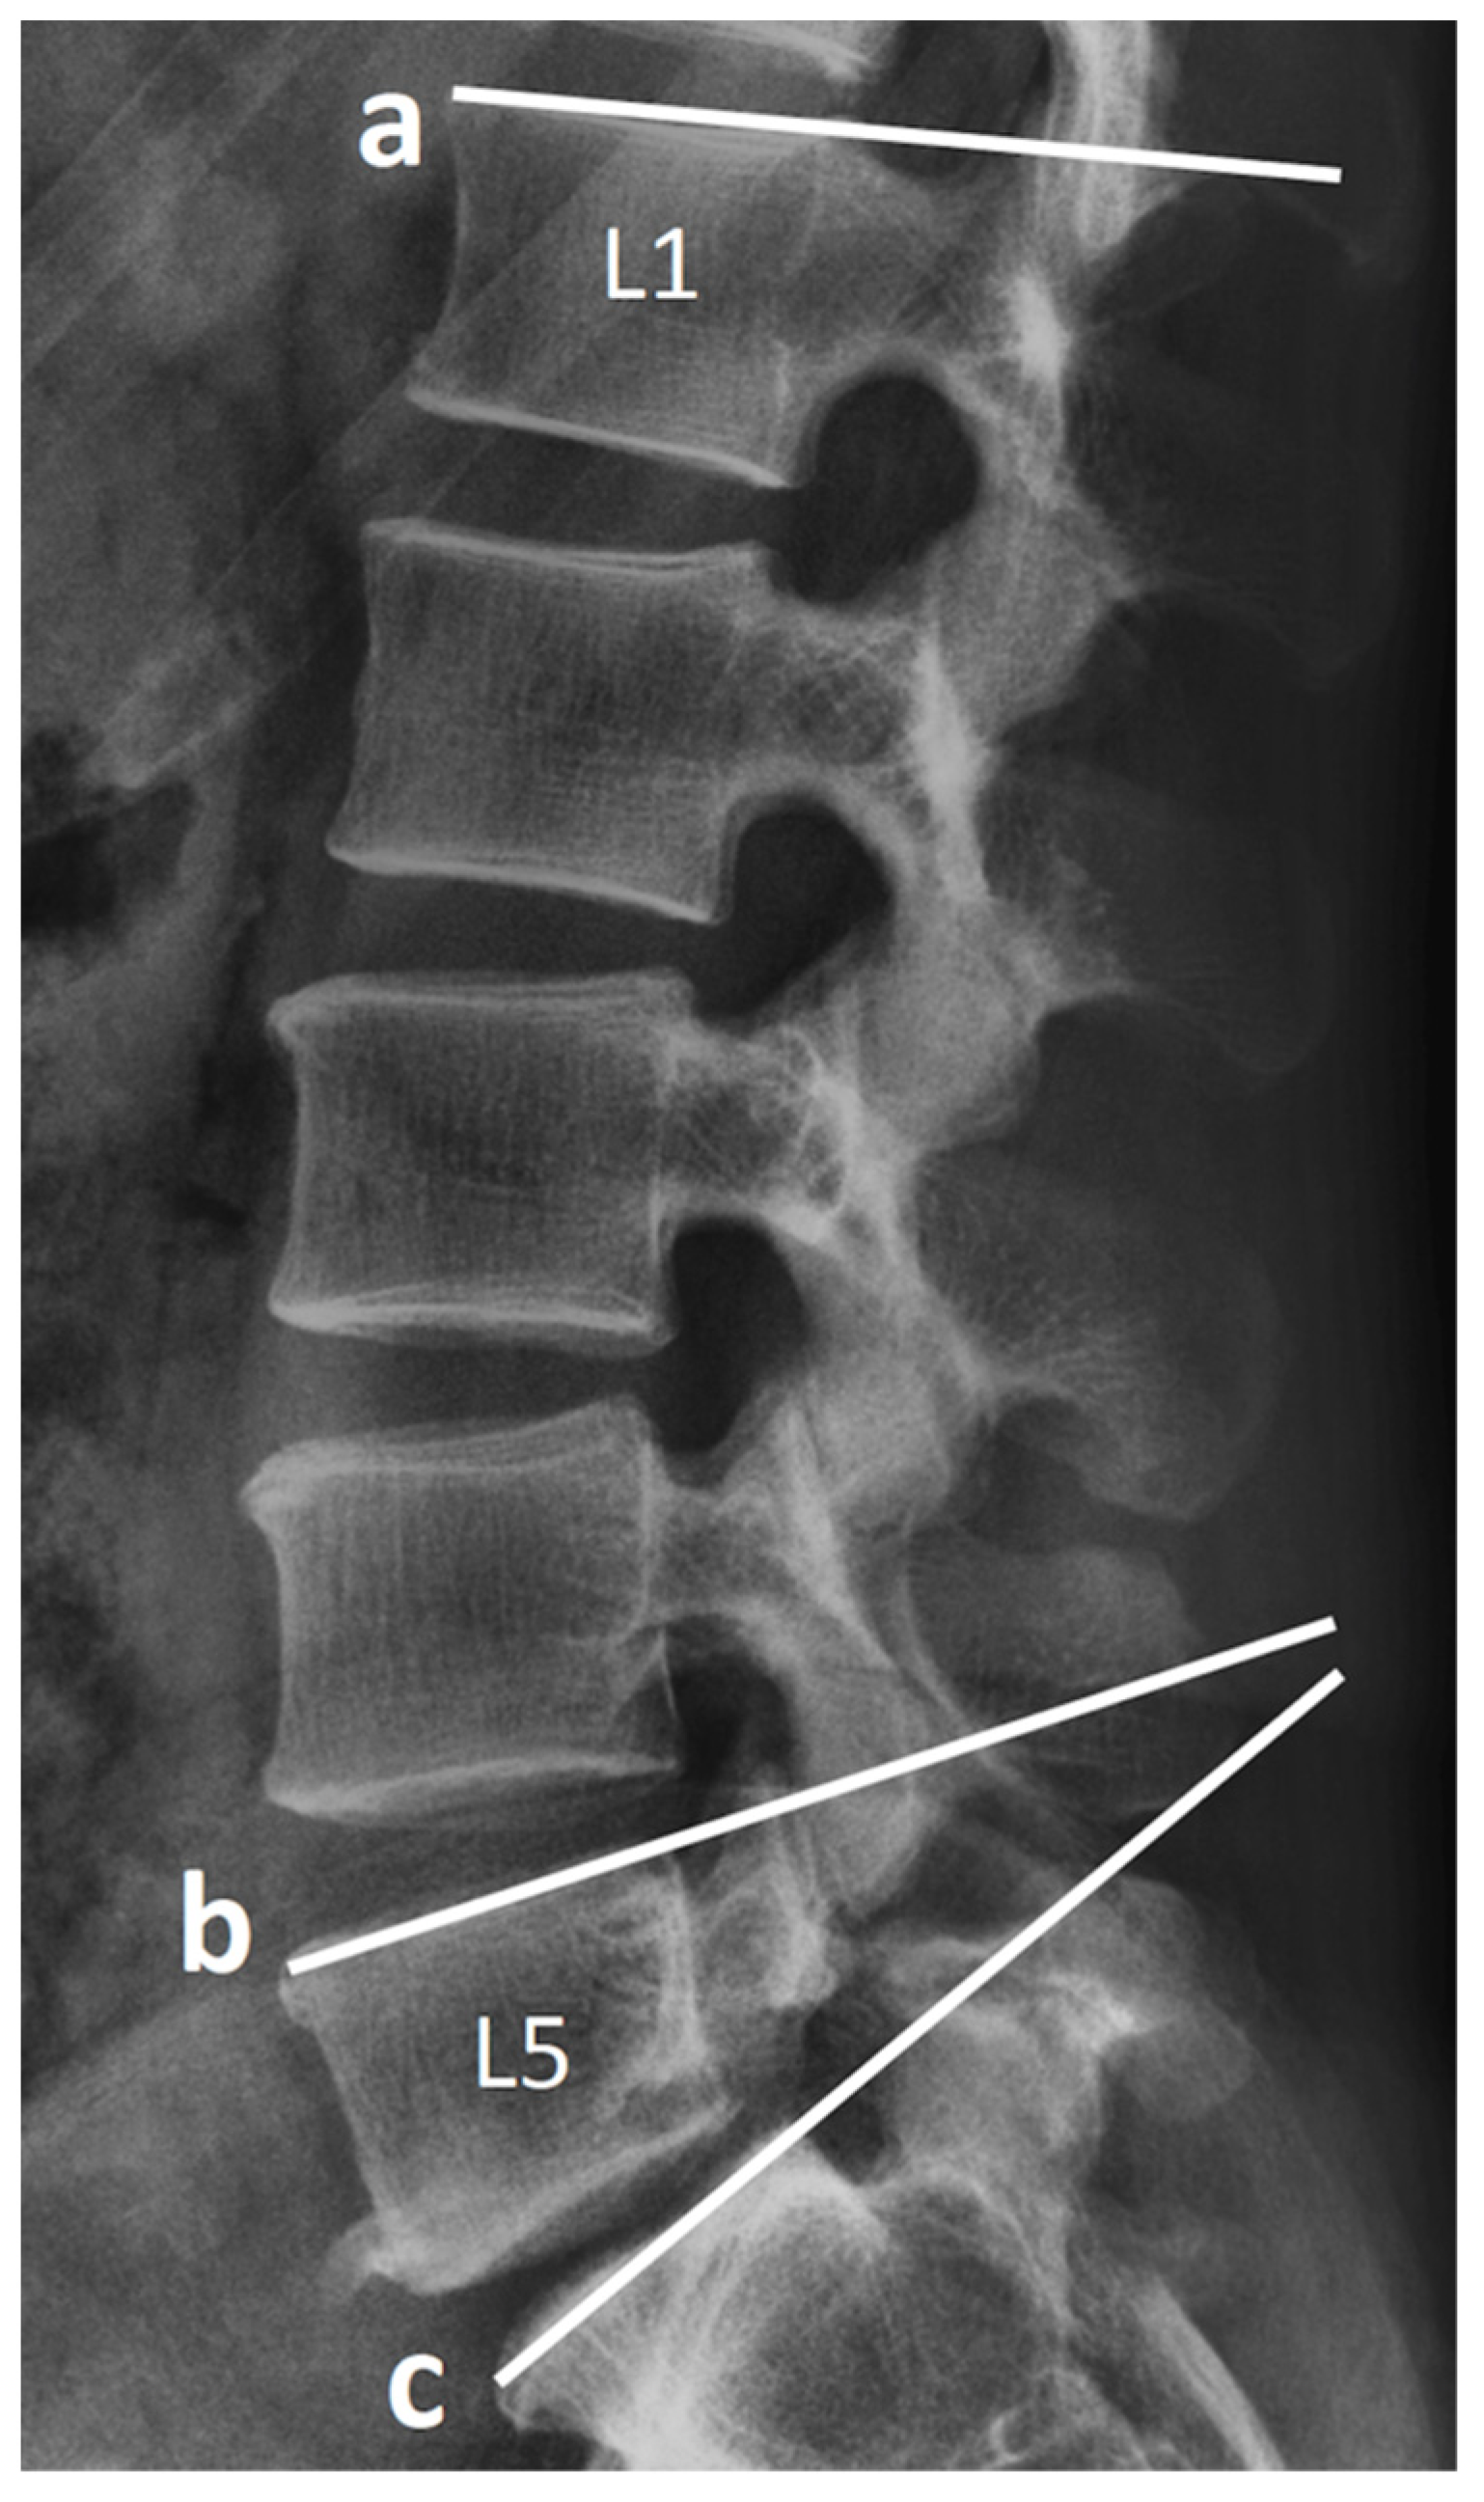

2.3. Radiological Assessment and Clinical Record